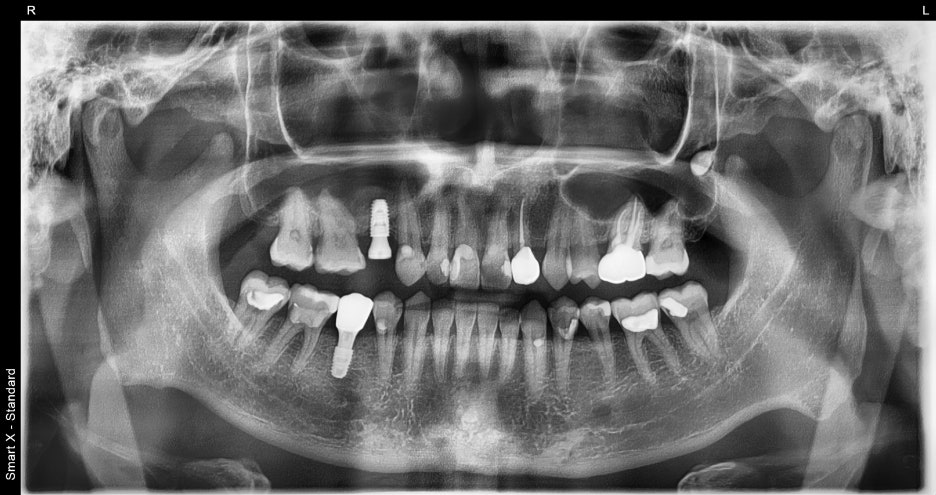

1.파노라마 촬영 결과, 오른쪽 아래 어금니는

치아가 파절되어 보존이 불가능했습니다.

발치 후 즉시 임플란트 식립이 가능한

상태로 진단되었습니다.

2.오른쪽 위 작은 어금니는 오래 전

상실된 치아였으나, 잇몸뼈의 흡수 정도가 심하지 않아

추가적인 뼈이식 없이 임플란트가 가능했습니다.

1회차: #45 발치 + 즉시 임플란트,

#15 임플란트 동시 식립

2~3회차: 치유 및 골유착 과정 점검

4회차: 최종 보철물 장착

→ 총 약 3개월 소요, 4회 내원으로 완성